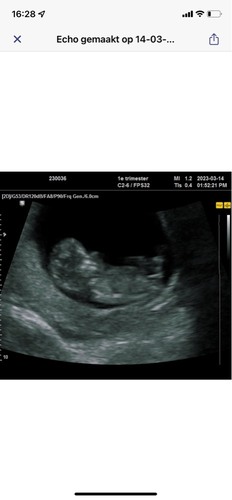

Wat denken jullie? 10+4🥰

Wie waagt de gok? 🩵🩷 10+4